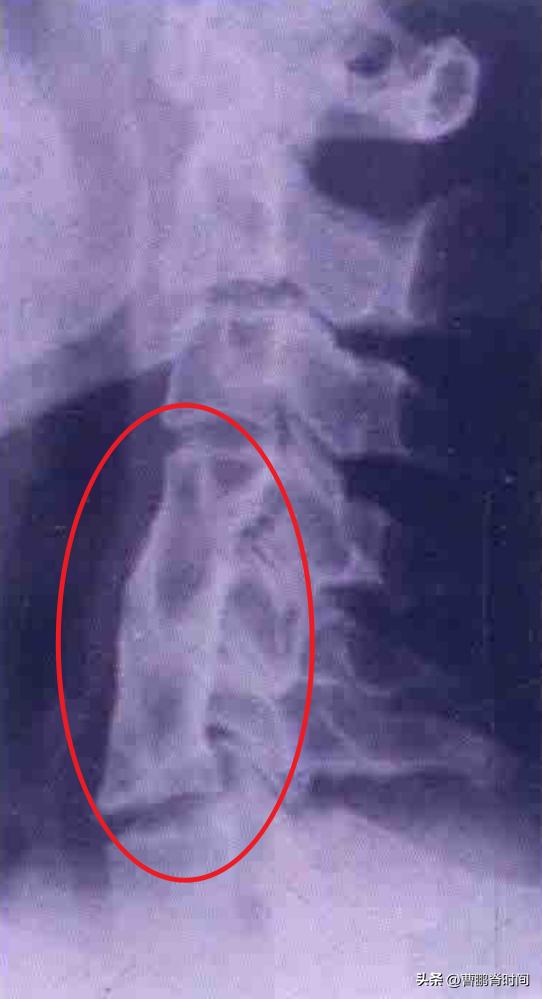

短颈综合征,又称先天性颈椎融合畸形,是指两个个或以上的 颈椎骨质先天性融合 。

颈椎是由 七节椎骨 组成,短颈综合征就占了两个或以上颈椎节段的融合和发育不良,自然会引起颈部的 长度缩短 和 活动受限 。